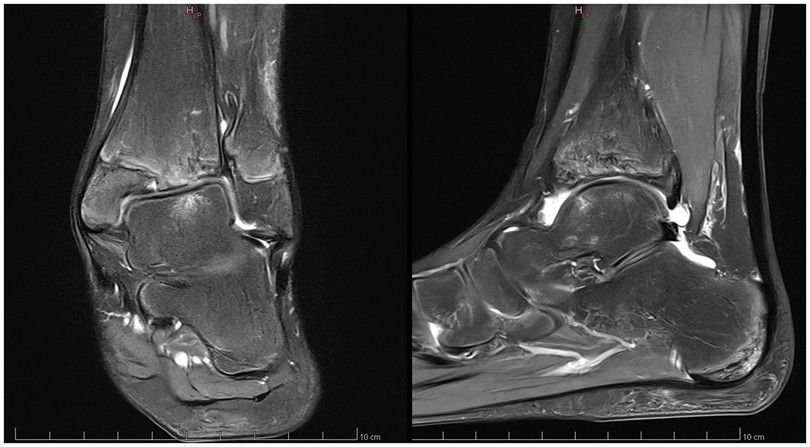

Anamnesis showed no family history of illness, genetic disorders, or osteochondrosis. The patient was 148 cm tall and weighed 37.5 kg, both measurements being one standard deviation above the mean. Clinical exam showed unrestricted, and symmetrical motion in the left ankle. There was a 13 mm leg length discrepancy on the left, and a standing hindfoot valgus angle of 10°. Palpation triggered pain in the joint's anterolateral aspect. Pain was noted over the anterior talofibular ligament with palpation, tension, weight-bearing, and tiptoe walking. The initial x-ray image of the left ankle revealed an irregularity of the distal tibia, with thinning or even an absence of the lateral epiphysis. The physis itself appeared scalloped and was difficult to clearly distinguish on its lateral side. A standing x-ray image of both ankles was taken, and radiographic alignment analysis revealed valgus of the joint line of the left ankle, with a mechanical distal lateral tibial angle measured at 76° (Figure 1). Unexpectedly, we identified trophic disturbances in the distal epiphysis of the contralateral tibia, indicating the presence of bilateral osteochondrosis. Indeed, the right epiphysis appeared to be both atrophic and sclerotic, but without fragmentation. A CT scan confirmed the fragmentation of the left epiphysis and a complete disruption of the physis on its lateral side. In certain instances, the imaging findings were indicative of possible physeal bars (Figure 2). MRI also confirmed the fragmentation and subsequent involution of the distal tibial epiphysis. It also revealed severe focal alterations in the physis and important metaphyseal deformities consecutive to abnormal endochondral ossification, as well as serious structural alterations in the articular cartilage (Figure 3). No lateral ligamentous or syndesmotic instability, nor rupture, was evident. A diagnosis of bilateral osteochondrosis of the distal tibial epiphysis was made, and the patient was prescribed a symptomatic treatment involving a prohibition of any sports activities and temporary immobilization in a left plaster cast for four weeks without weightbearing due to pain.

Figure 3. This MRI of the left ankle confirmed the epiphyseal fragmentation, the physeal abnormalities and the metaphyseal deformities.